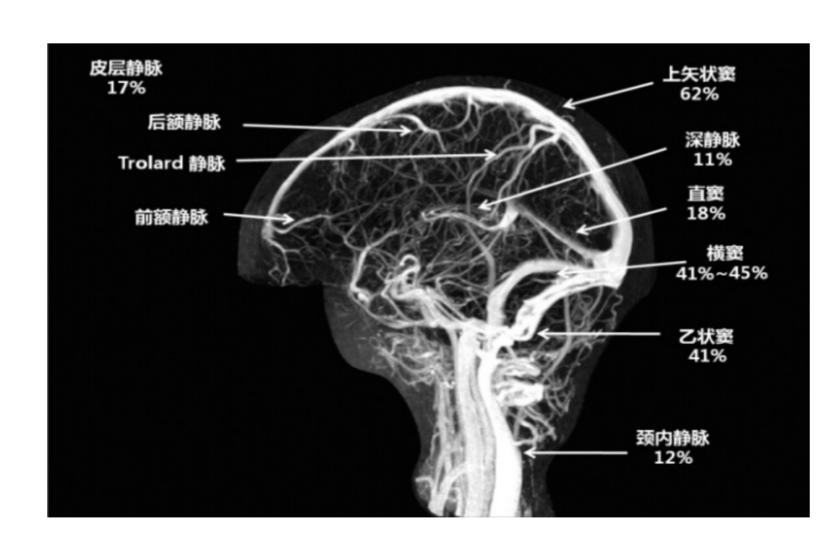

I.直接征象:静脉窦内三角形或条带状高密度影。当血栓位于大脑皮层浅静脉,可见条带状高密度影,即为“束带征”(图2)。当血栓位于上矢状窦后部,表现为圆点或者三角状高密度影,即为“三角征”(图3)。

图2 CT提示左侧横窦高密度影,即束带征

图3 CT平扫提示上矢状窦类圆形高密度影,即三角征II.间接征象:包括脑水肿、脑梗死或颅内出血等。